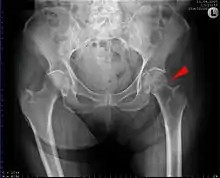

A hip fracture is a break that occurs in the upper part of the femur (thigh bone), at the femoral neck or (rarely) the femoral head.[2] Symptoms may include pain around the hip, particularly with movement, and shortening of the leg.[2] Usually the person cannot walk.[3]

| Intertrochanteric hip fracture in a 17-year-old male | |

X-rays of the affected hip usually make the diagnosis obvious; AP (anteroposterior) and lateral views should be obtained.